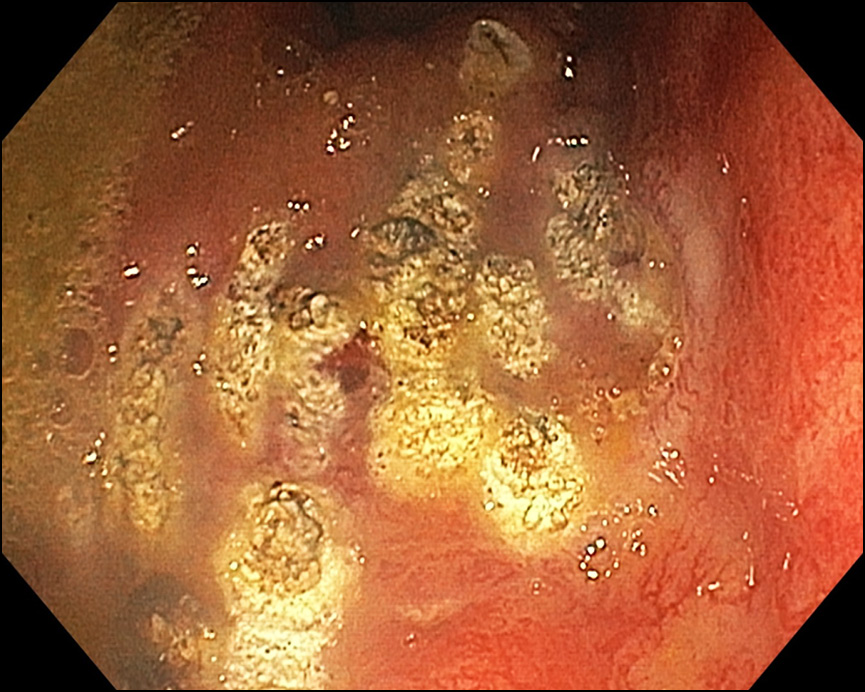

Рис. 2. Состояние после аргоноплазменной коагуляции ангиэктазий (25.11.2019)

Учитывая рецидивирующие ректальные кровотечения, пациенту было рекомендовано эндоскопическое лечение. 25.11.2019 выполнена аргоноплазменная коагуляция ангиэктазий по передней стенке прямой кишки (рис. 2).

После выполнения процедуры самочувствие пациента улучшилось, примесь крови при дефекации практически исчезла. 02.12.2019 пациенту выполнен 2-й этап лечения: в нижнеампулярном отделе прямой кишки определяются множественные ангиэктазии диаметром 2−5 мм, местами сливающиеся, единичные контактно кровоточат. Определяется коагуляционный некроз (аргоноплазменная коагуляция от 25.11.2019), под фибрином вкрапления гематина размером около 2,0 × 1,5 см (рис. 3). Выполнена аргоноплазменная коагуляция крупных и сливных ангиэктазий по всем стенкам.